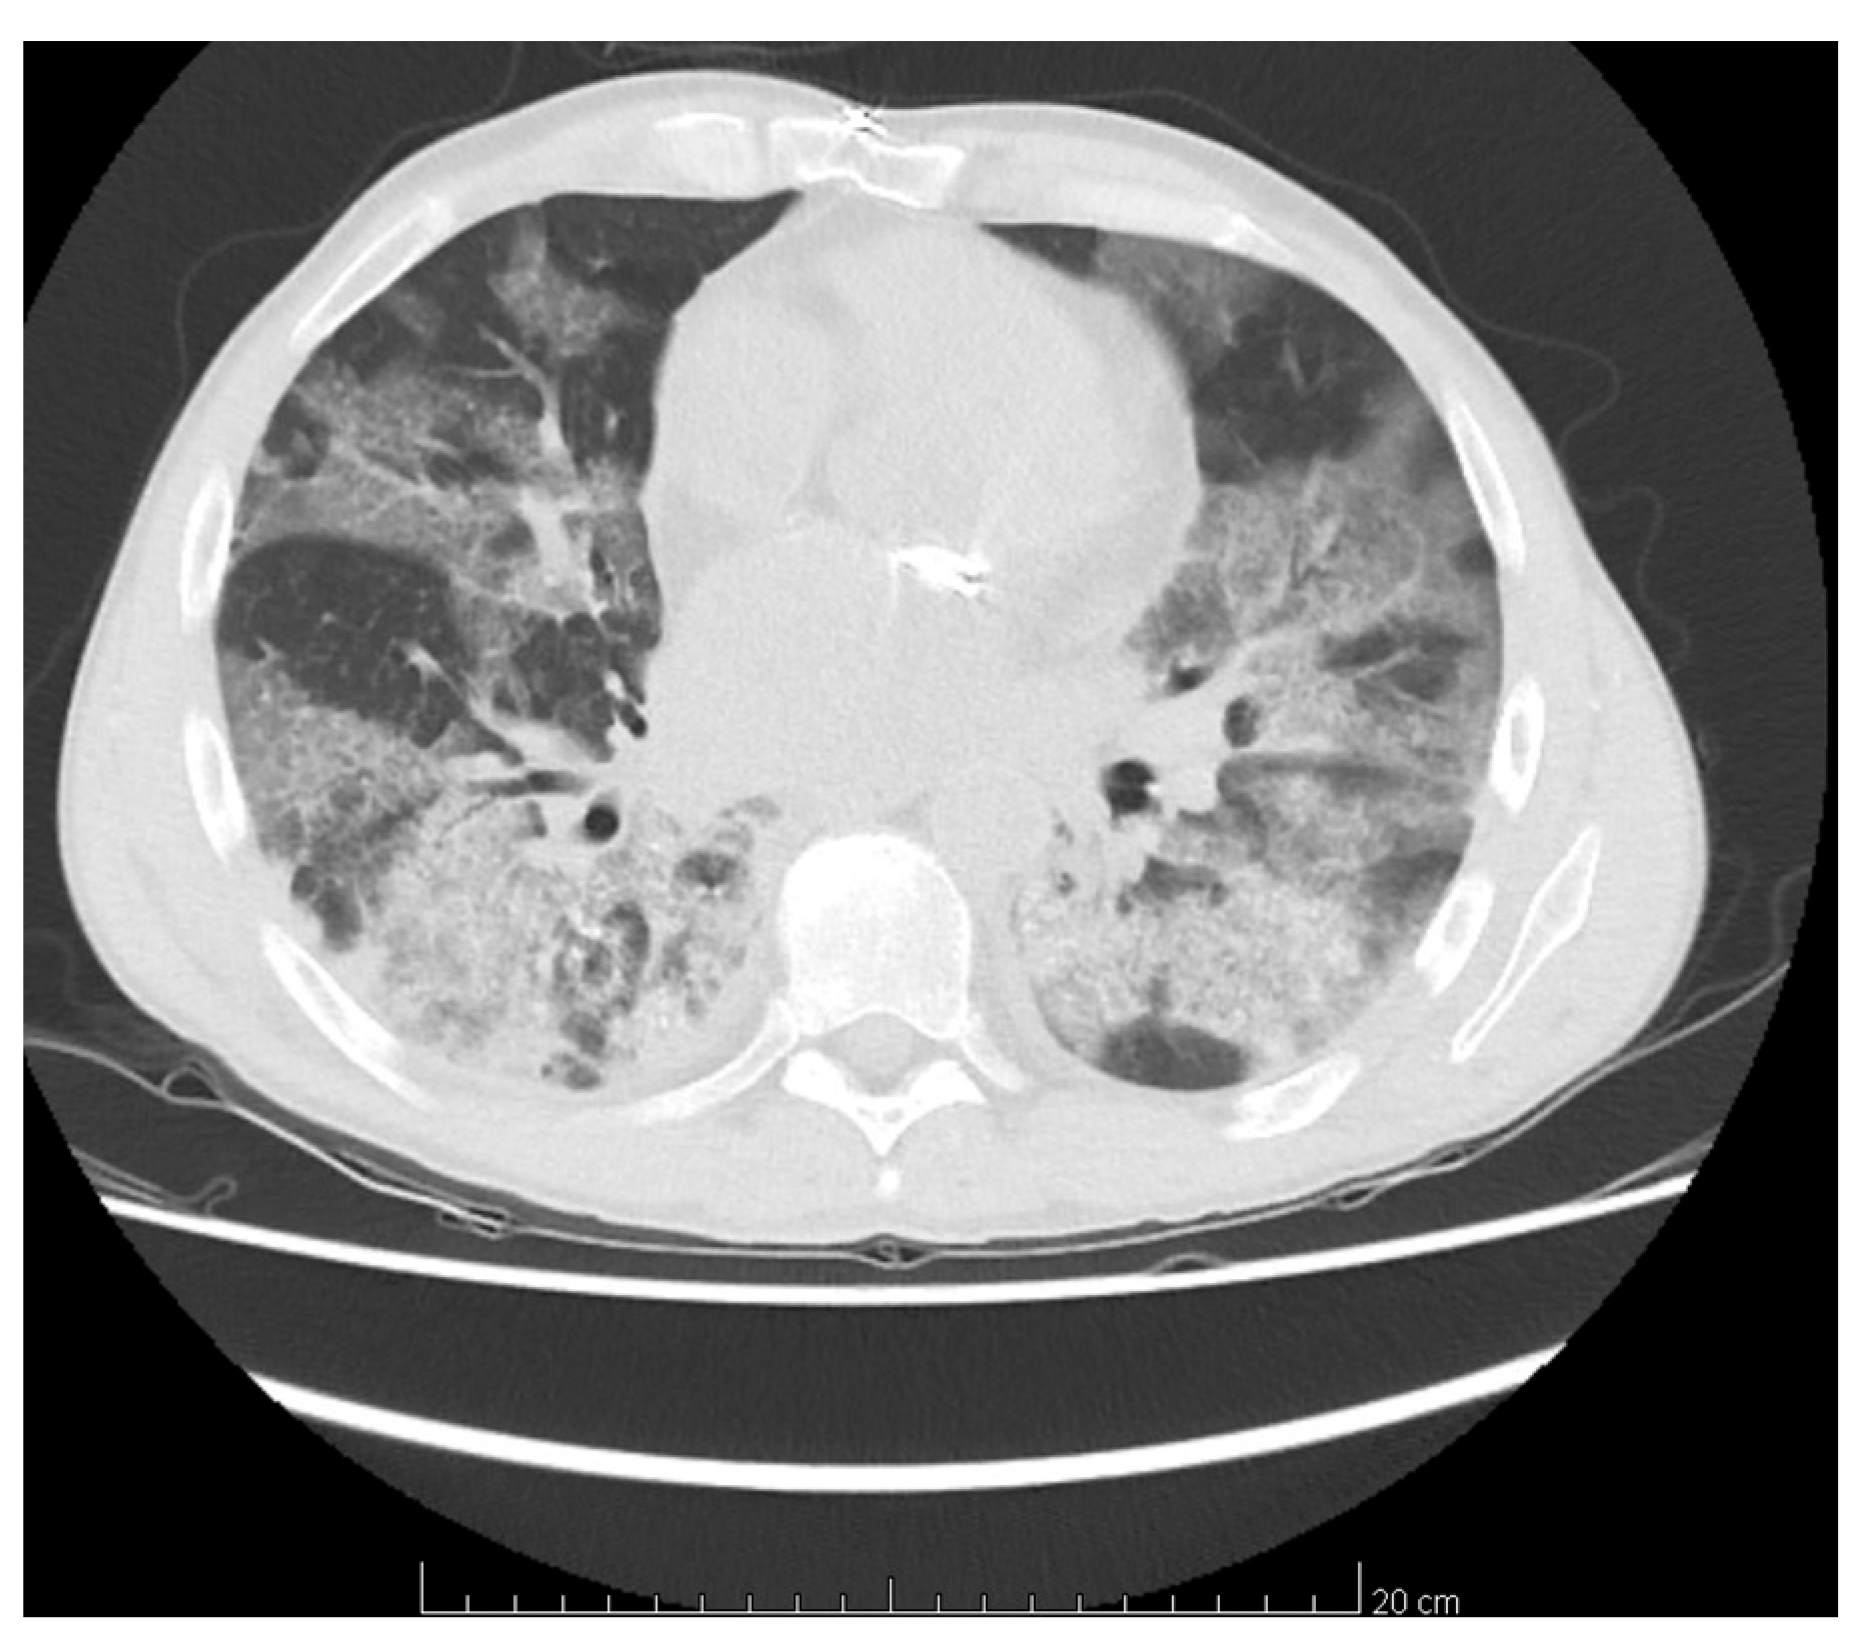

His chest computer tomography (CT) showed wide areas of bilateral ground-glass opacities with segmental areas of crazy paving and local inflammation (Figure 1). Respiratory therapy and continuous hemodialysis (HD) were implemented and he received dexamethasone in dose of 12 mg per day with wide-spectrum antibiotic therapy (meropenem and vancomycin, followed by linezolid), MMF was stopped at once while TAC dose was first reduced and then discontinued a few days later. He required red blood cells (RBCs) transfusion. Remdesivir was not administered due to a long interval between diagnosis of COVID-19 infection and treatment, nor was tocilizumab due to high PCT levels. After two negative Abbott COVID-19 tests, his isolation was ended. In the third week of hospitalization an improvement of general status was observed, patient was extubated, his diuresis gradually resumed and graft function improved so HD was stopped and he was transferred to nephrology department two days later for further treatment in general semi-severe condition. On admission to nephrology, he was cachectic, lying down with visible dyspnea at any movement and still dependent on oxygen mask with reservoir, with oxygen flow 14 L/min. There were also present symptoms of oral candidiasis and diarrhea of clostridium difficile etiology so the treatment with itraconazole and vancomycin orally and metronidazole intravenously was started. On admission his inflammatory markers were high (CRP 353.6 mg/L; PCT 4.13 ng/mL; see Table 1. Part C) so he was tested and found positive for both bacterial (Enterococcus faecium, Klebsiella pneumoniae) and fungal (Candida glabrata) infection in the urinary tract as well as blood infection (Staphylococcus epidermidis). Targeted antibiotics (teicoplanin, meropenem) were administered. CMV DNA was also detected and valganciclovir was started. Throughout the whole hospitalization, the patient required rehabilitation and nutritional treatment with gradually expanded oral diet. The therapy resulted in improvement of his general status with disappearance of inflammation signs and dyspnea. During hospitalization RT-PCR COVID-19 tests were performed four times as per local standards—all were negative; IgM and IgG concentrations were not assessed. The patient had diuresis (2 L/day) with satisfactory stable graft function (serum creatinine [sCr] 2.5–3.2 mg/dL) and immunosuppressive treatment was implemented again, first TAC with trough level around 5 ng/mL and dexamethasone was converted to prednisone. Then MMF treatment was restarted in reduced dose (500 mg/day) on discharge on day 39 of hospitalization.

Clinical presentation of SARS-CoV-2 in KTx recipients ranges from mild to severe, including multiorgan failure and death [12]. Our patient presented typical and most common symptoms of COVID-19 disease observed both in general [11] as well as in KTx population [10,14,15] before finally developing acute respiratory distress syndrome (ARDS) which is one of the most critical manifestations [14]. Maybe in order to prevent further complications we should have recommended at that stage a modification of immunosuppressive treatment (MMF dose reduction together with the increasing dose of glucocorticosteroids) and conversion of VKA to LMWH. However, due to a remote place of residence, the patient was not able to come to the outpatient posttransplant clinic so the laboratory tests and full medical investigation could not be performed at the specialist center earlier and only symptomatic treatment was recommended. Lymphopenia, which was observed in our case, is common in persons infected with COVID-19 in general population [11] as well as in KTx [15] and is associated with severity of the disease [16], but it can be a consequence of immunosuppressive therapy as well [17]. Our patient had decreased platelet count and elevated CRP, PCT, D-dimer, lactate dehydrogenase (LDH), creatine kinase (CK), and creatinine which in meta-analysis of 32 studies including 10,491 patients with confirmed COVID-19 are considered to be indicators of poor outcomes, as well as elevated ALT and AST [18]; however, the latter two parameters were normal in the presented case. Bilateral infiltrations with the image of frosted glass in our patient’s lungs are most common abnormalities described in patients with SARS-CoV-2 infection [14]. The most frequently observed complication of COVID-19 in general population is sepsis caused by bacteria, followed by ARDS and multiorgan insufficiency including kidney failure [11] which all occurred in herein presented patient. At the beginning of COVID-19 infection our patient, due to mild symptoms, was treated symptomatically at home and no modification of immunosuppression was recommended, but as his general condition worsened and he was eventually admitted to ICU, MMF was suspended together with reduction of the TAC dose and discontinued when the patient required respiratory therapy. Such procedure is recommended by experts although different centers have different strategies with regard to the risk of graft rejection [9]. That is why it is necessary to formulate proper management of immunosuppression and further guidelines in the treatment of COVID-19 in the transplant population. Our patient did not receive remdesivir because of a long interval between diagnosis and treatment of COVID-19, nor tocilizumab due to high PCT levels. He was treated only with dexamethasone and received broad-spectrum antibiotic therapy.

Figure 1. Computer tomography scan revealed wide areas of bilateral ground-glass opacities with segmental areas of crazy paving and local inflammation.